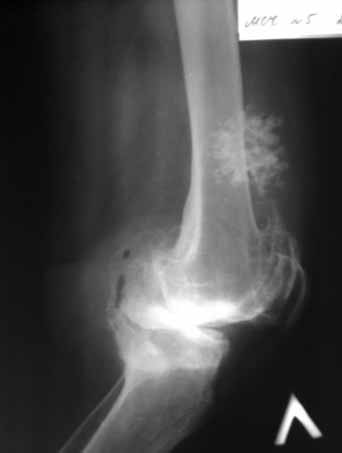

Пациентка 72 лет.Не обследовалась и не лечилась.

Работала поварихой до последнего времени. обратилась за медпомощью впервые. ходит без

дополнительной опоры. Основные жалобы на ограничение движений и боли в правом коленном

суставе. Финансовые возможности ограничены. Чем можно помочь? Артродез? Протезирование?